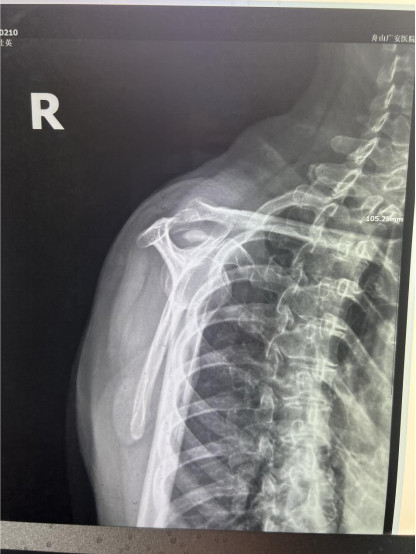

賀大媽慕名來(lái)廣安醫(yī)院找羅軍主任就診,面對(duì)羅醫(yī)生,賀大媽哭訴:“羅醫(yī)生,我真想剁下自己的這只胳膊。”羅軍主任根據(jù)患者的癥狀拍片,診斷為岡上肌鈣化性肌腱炎,隨后,羅醫(yī)生為李大媽進(jìn)行了肩關(guān)節(jié)鏡微創(chuàng)手術(shù),竟從她的右肩“擠”出“牙膏”。

是不是只要病人撐得住,讓鈣鹽吸收就沒(méi)事了?羅軍主任表示,經(jīng)保守治療無(wú)法緩解或病程長(zhǎng)的患者,應(yīng)盡早采取手術(shù)治療。而且,部分患者鈣鹽無(wú)法完全吸收,拖下去只會(huì)使病情惡化,造成肩膀肩袖肌腱的損傷。

羅軍主任表示,很多人會(huì)把肩痛都?xì)w因于肩周炎,這是一個(gè)很大的誤區(qū)。其實(shí),肩痛人群中只有15%左右是肩周炎,大部分肩膀疼痛由于肩袖損傷、肩峰撞擊征、鈣化性肌腱炎。而大多數(shù)人也因此認(rèn)為忍一忍就會(huì)自愈,常常延誤治療,關(guān)節(jié)鏡微創(chuàng)治療鈣化性肌腱炎,可以快速緩解疼痛,同時(shí)可以修復(fù)肩袖損傷,清理肩膀骨刺。